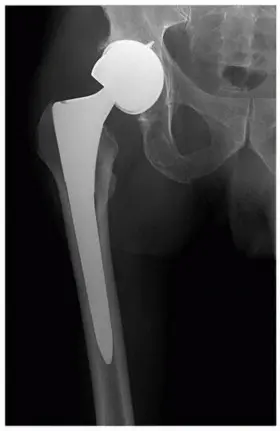

عندما يتضرر مفصل الورك بشكل لا يمكن علاجه بالطرق التقليدية، قد يوصي الأطباء بإجراء استبدال مفصل الورك الكلي. تتضمن هذه الجراحة إزالة الأجزاء التالفة من العظم والغضروف واستبدالها بمكونات صناعية:

* المكون الفخذي (Femoral Component): يتكون عادةً من ساق معدنية تُدخل في عظم الفخذ، وكرة معدنية أو خزفية تحل محل رأس عظم الفخذ.

* المكون الحُقِّي (Acetabular Component): يتكون من كوب معدني يُثبت في الحُق، وبطانة بلاستيكية (بولي إيثيلين)، أو خزفية، أو معدنية داخل الكوب لتعمل كسطح تحمل.

تهدف هذه الجراحة إلى تخفيف الألم واستعادة وظيفة المفصل الطبيعية. ومع ذلك، قد تحدث مشاكل مع هذه المكونات بمرور الوقت، مما يستدعي الحاجة إلى جراحة المراجعة.